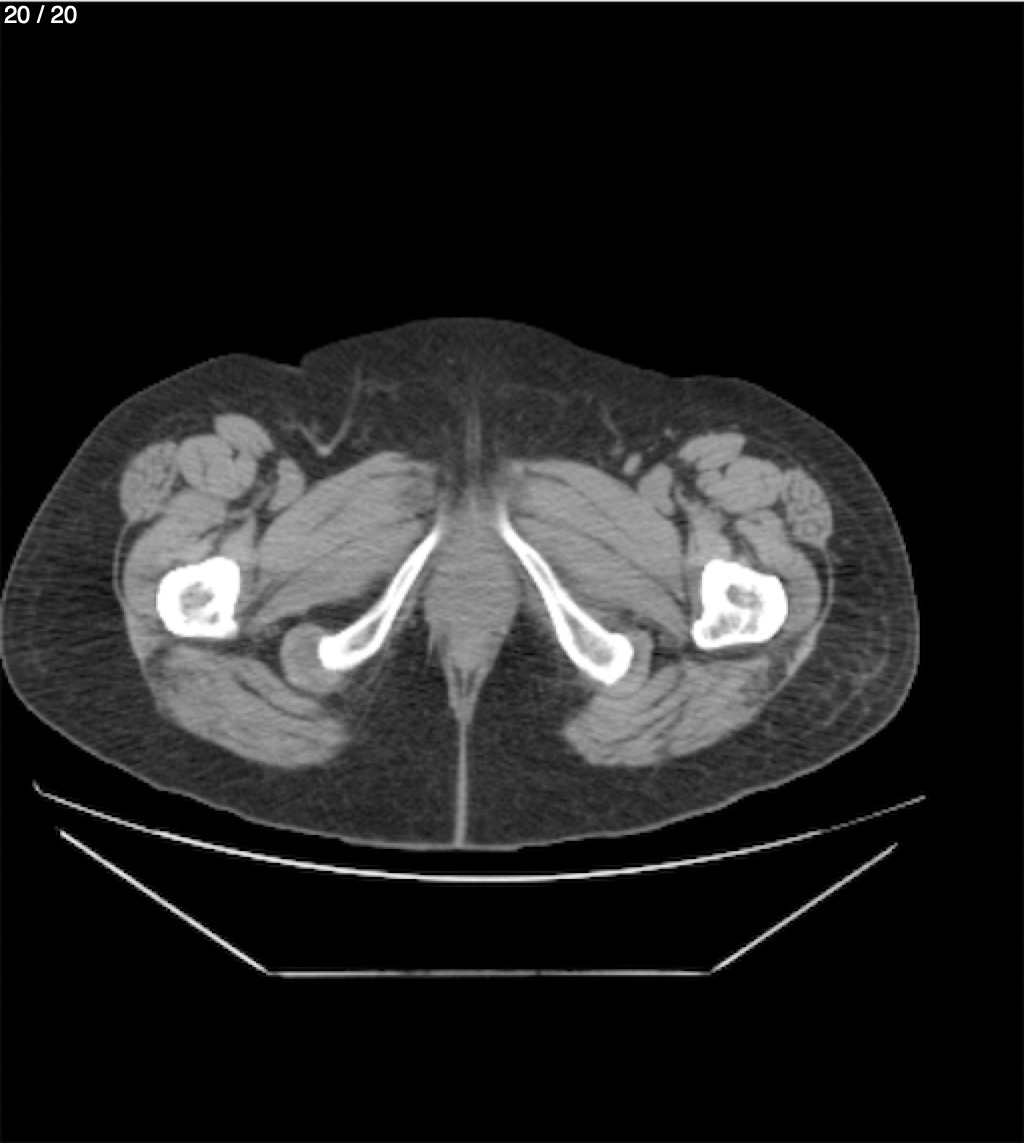

Maria Enrique Giron Dominguez63A - T.C Abdomen Simple